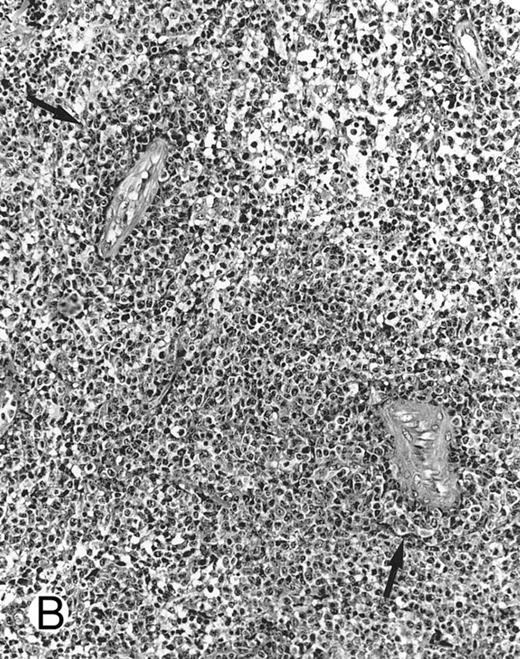

Lymph node biopsy of aggressive NK cell leukemia/lymphoma (case no. 37). There is a fairly monotonous, diffuse infiltrate of medium-sized cells with round nuclei. The neoplastic cells in this case resemble plasmacytoid monocytes.

There were very few to numerous granular lymphocytes in the peripheral blood. Some of the granular lymphocytes were indistinguishable from normal large granular lymphocytes, with round nuclei, dense chromatin, and pale cytoplasm with fine azurophilic granules (Fig 5A). Some granular lymphocytes had larger nuclei with more open chromatin and distinct nucleoli (Fig 5B); occasional nuclei could show indentations. The azurophilic granules were sometimes large and coarse. There were also circulating normoblasts and immature myeloid cells. Marrow involvement ranged from subtle to extensive. In histologic sections, irrespective of site, there was a monotonous infiltrate of medium-sized cells with round nuclei and fairly condensed chromatin (Fig 6). Karyorrhexis was prominent. The infiltrate was diffuse, interstitial, or angiocentric.